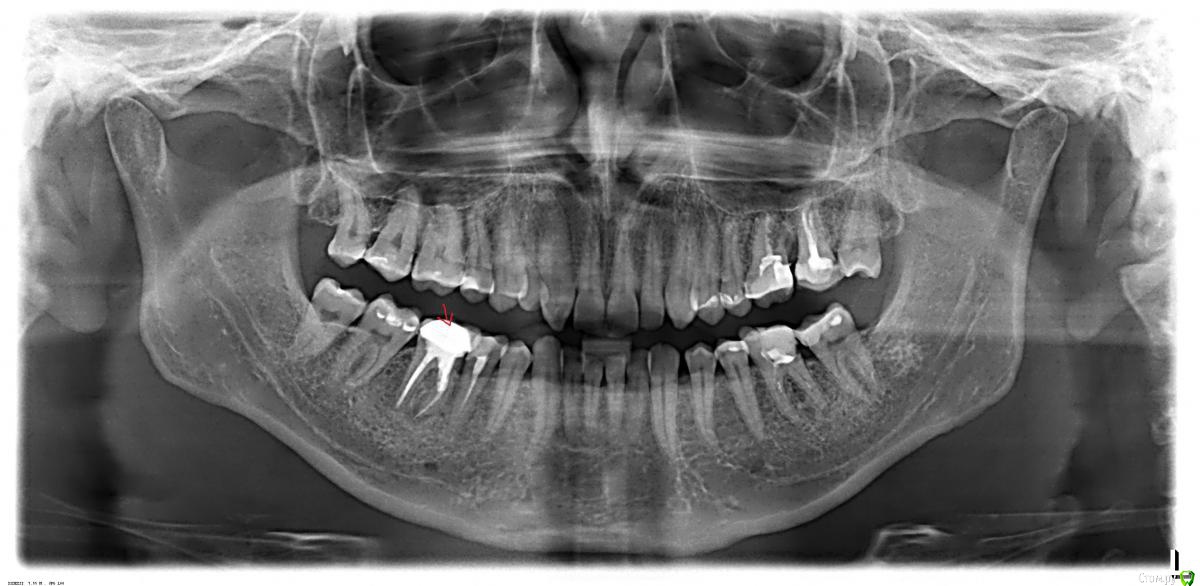

Капустин Роман Опубликовано 13 мая, 2018 Поделиться Опубликовано 13 мая, 2018 Добрый день! Нахожусь по работе в Никарануа г.Манагуа до декабря 2018 года. Стоит коронка с 2013 года. После чистки с внутренней стороны десны появился шарик. Врач предлагает удалить и поставить имплант. Хочется сохранить зуб. Насколько возможно? Спасибо. Ссылка на комментарий

Bier Опубликовано 13 мая, 2018 Поделиться Опубликовано 13 мая, 2018 к сожалению для Вас, врач похоже прав. Ссылка на комментарий